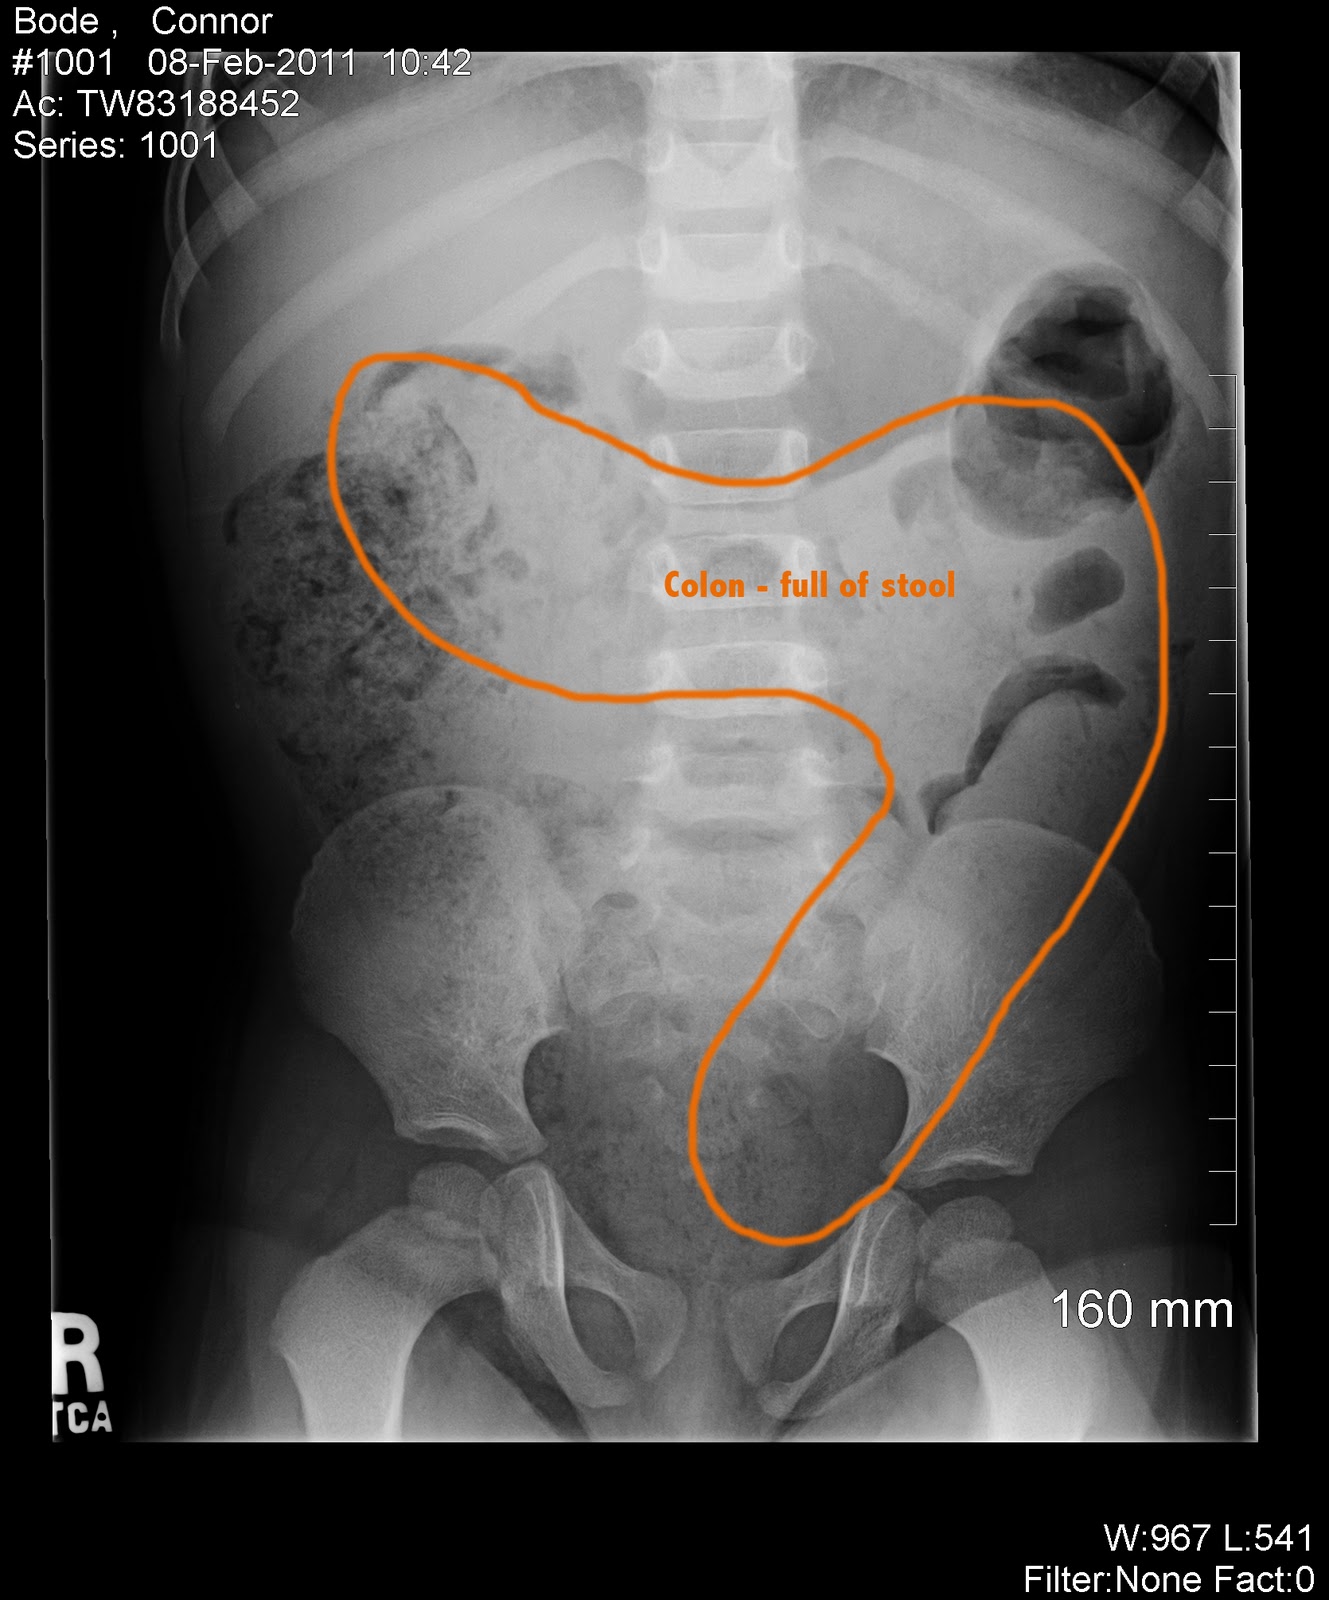

From www.pinterest.com

Pin on thexraydoctor Backed Up Stool On X Ray A fecal impaction is a large, hard mass of stool that gets stuck so badly in your colon or rectum that you can’t push it out. Fecal impaction is the result of severe constipation, when you're unable to regularly pass poop (stool or feces) and it backs up inside. Fecal impaction is most commonly a complication of chronic or severe. Backed Up Stool On X Ray.